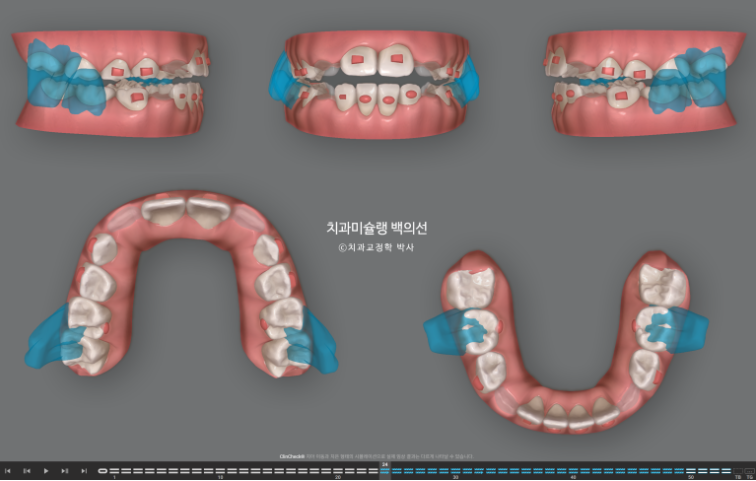

치료계획은 전반부의 악궁확장 및 덧니해소 단계와 후반부의 MA를 통한 하악성장 유도 두단계로 나뉩니다.

전반부 장치 갯수는 23개로 약 6개월이 예상되고

후반부에는 24단계부터 53단계까지 MA 단계입니다.

장치 양옆에 날개처럼 튀어나온 부분이 Wing 이며 이 부분이 아래턱의 위치를 정상위로 유도합니다.

사진의 파란화살표처럼 위 아래 윙 끼리 엇갈려 물리며 아래턱을 전방위치 시키며, 최대성장기와 맞물리면 하악골 성장까지 유도하게 됩니다.